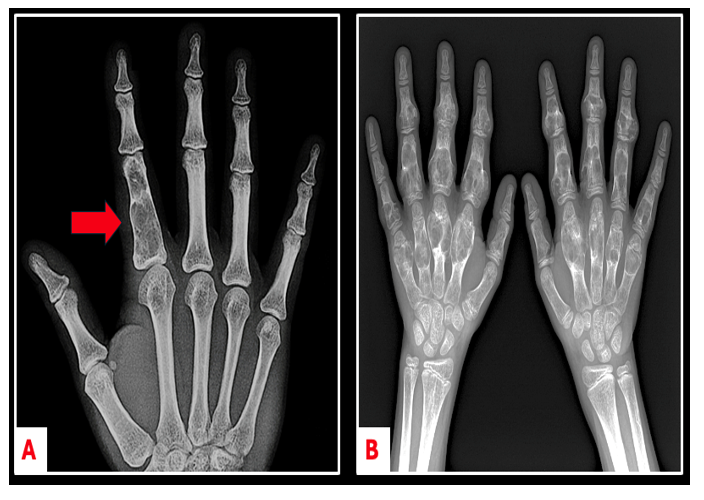

On an X-ray, enchondromas look like an area with white, popcorn-like spots in the middle of the bone (Figure 1). In small bones like the fingers and toes, the bone around the bump may look a little wider or expanded (Figure 2A).

There is a rare condition called Ollier disease (also known as enchondromatosis) in which people develop multiple enchondromas in different parts of their body (Figure 2B). Ollier disease occurs in about 1 out of every 100,000 people. A related condition, called Maffucci syndrome, also causes multiple enchondromas but includes benign blood vessel growths (called hemangiomas) in the skin or soft tissues. People with Ollier disease or Maffucci syndrome should see an Orthopedic Oncologist for regular check-ups, since they have a higher risk of developing a chondrosarcoma (a type of bone cancer). Most people, however, have just one enchondroma, and in those cases, the chance of it turning into cancer is very rare. These patients usually don’t need frequent check-ups or treatment.

Figure 2. Anterior-posterior (AP) imaging comparing a simple enchondroma of the hand (A) versus the numerous enchondromas found in Ollier Disease (i.e. enchondromatosis, B).